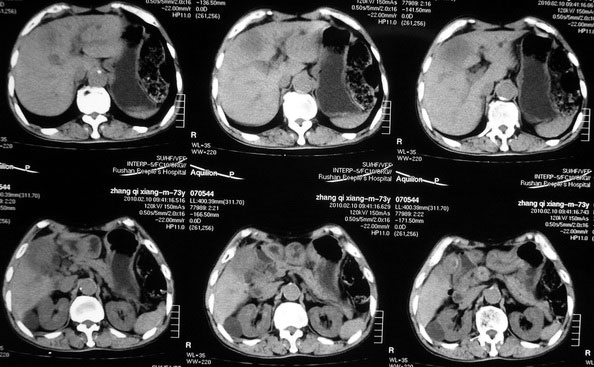

肝胆管细胞癌

患者AFP正常,无肝病病史。CA199 1000ng/ml,CEA偏高。血象WBC正常,N偏高。

化脓性胆囊炎累及肝脏;胆管细胞癌;肝转移瘤

活检病理

:是

胆管细胞癌

这个病人开始就是主要鉴别的肝脓肿和胆管细胞癌。可是增强后环征也不明显,占位内造影也非常不明显。这种情况怎么判断?谢谢大家。

病灶强化幅度较轻,低密度坏死区内见无定形高密度影,是其特点。